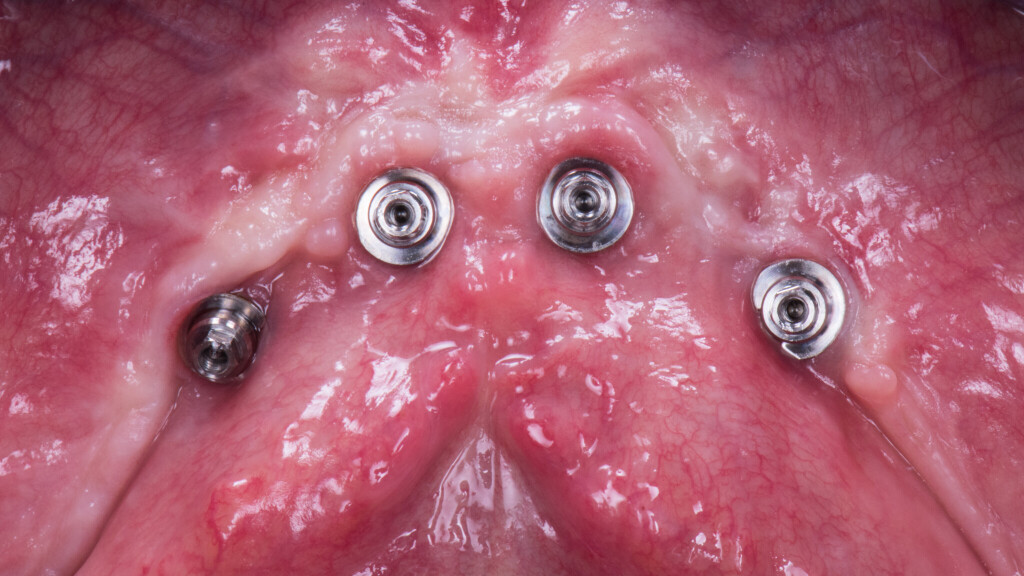

Qui vedi la guarigione a 3 mesi: